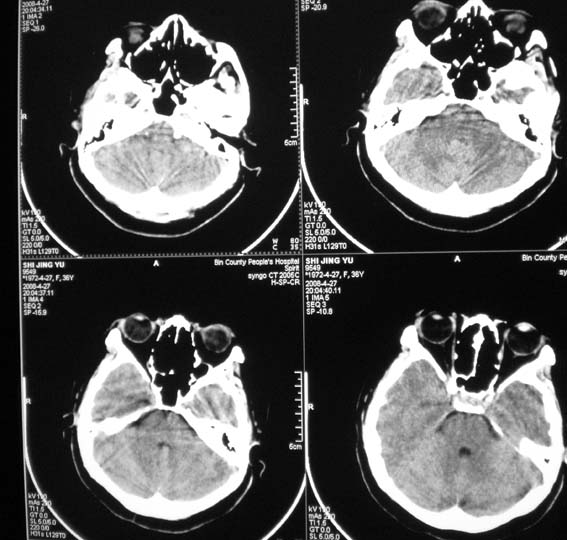

标题: CT13124:女,36岁,常短暂性意识丧失。 [打印本页]

女,36岁,常短暂性意识丧失。

颅脑ct平扫未见明显异常。

右顶部放射冠部白质内异常灰质团块影 考虑灰质移位症可能

患者短暂性意识丧失考虑为癫痫小发作

另外要注意患者ecg或holter检查,以除外心源性晕厥可能

鞍上池右侧旁脑质内见团块稍高密度影,建议mr检查。